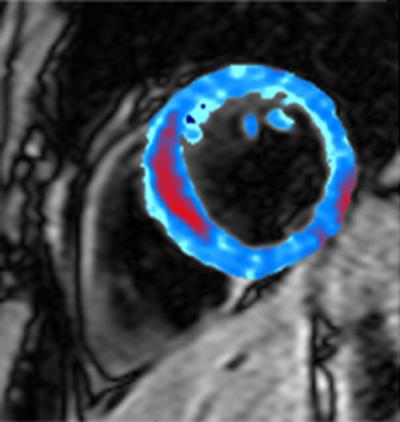

image: The colored area on this MRI scan shows a cross-section of the heart muscle, with the area of bleeding shown in red. view more

Images that for the first time show bleeding inside the heart after people have suffered a heart attack have been captured by scientists, in a new study published today in the journal Radiology.

The research shows that the amount of bleeding can indicate how damaged a person's heart is after a heart attack. The researchers, from the MRC Clinical Sciences Centre at Imperial College London, hope that this kind of imaging will be used alongside other tests to create a fuller picture of a patient's condition and their chances of recovery.

For the new small study, the researchers captured images of bleeding inside the heart in 15 patients from Imperial College Healthcare NHS Trust who had recently suffered a heart attack, using Magnetic Resonance Imaging (MRI). Analysis of the MRI scans revealed that the amount of bleeding correlated with how much damage the heart muscle had sustained.

Patients who had suffered a large heart attack, where a lot of the heart muscle was damaged, had a lot of bleeding into the heart muscle compared with those whose heart attack was relatively small.

The researchers were able to detect the area of bleeding because of the magnetic effects of iron, which is present in the blood.